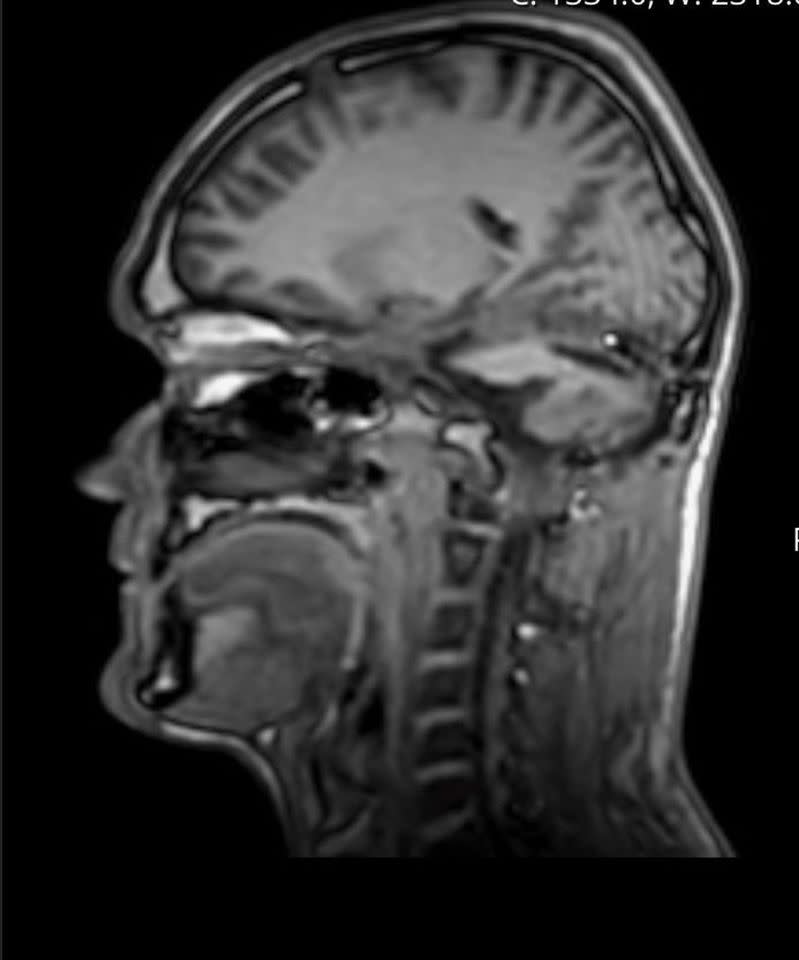

Luke Taylor’s brain scan

Credit: Nia Jones via SWNS

When the scans came back, Taylor was diagnosed with a haemangioblastoma, a rare benign brain tumor typically found in the cerebellum, which is essential for motor control and cognitive function.